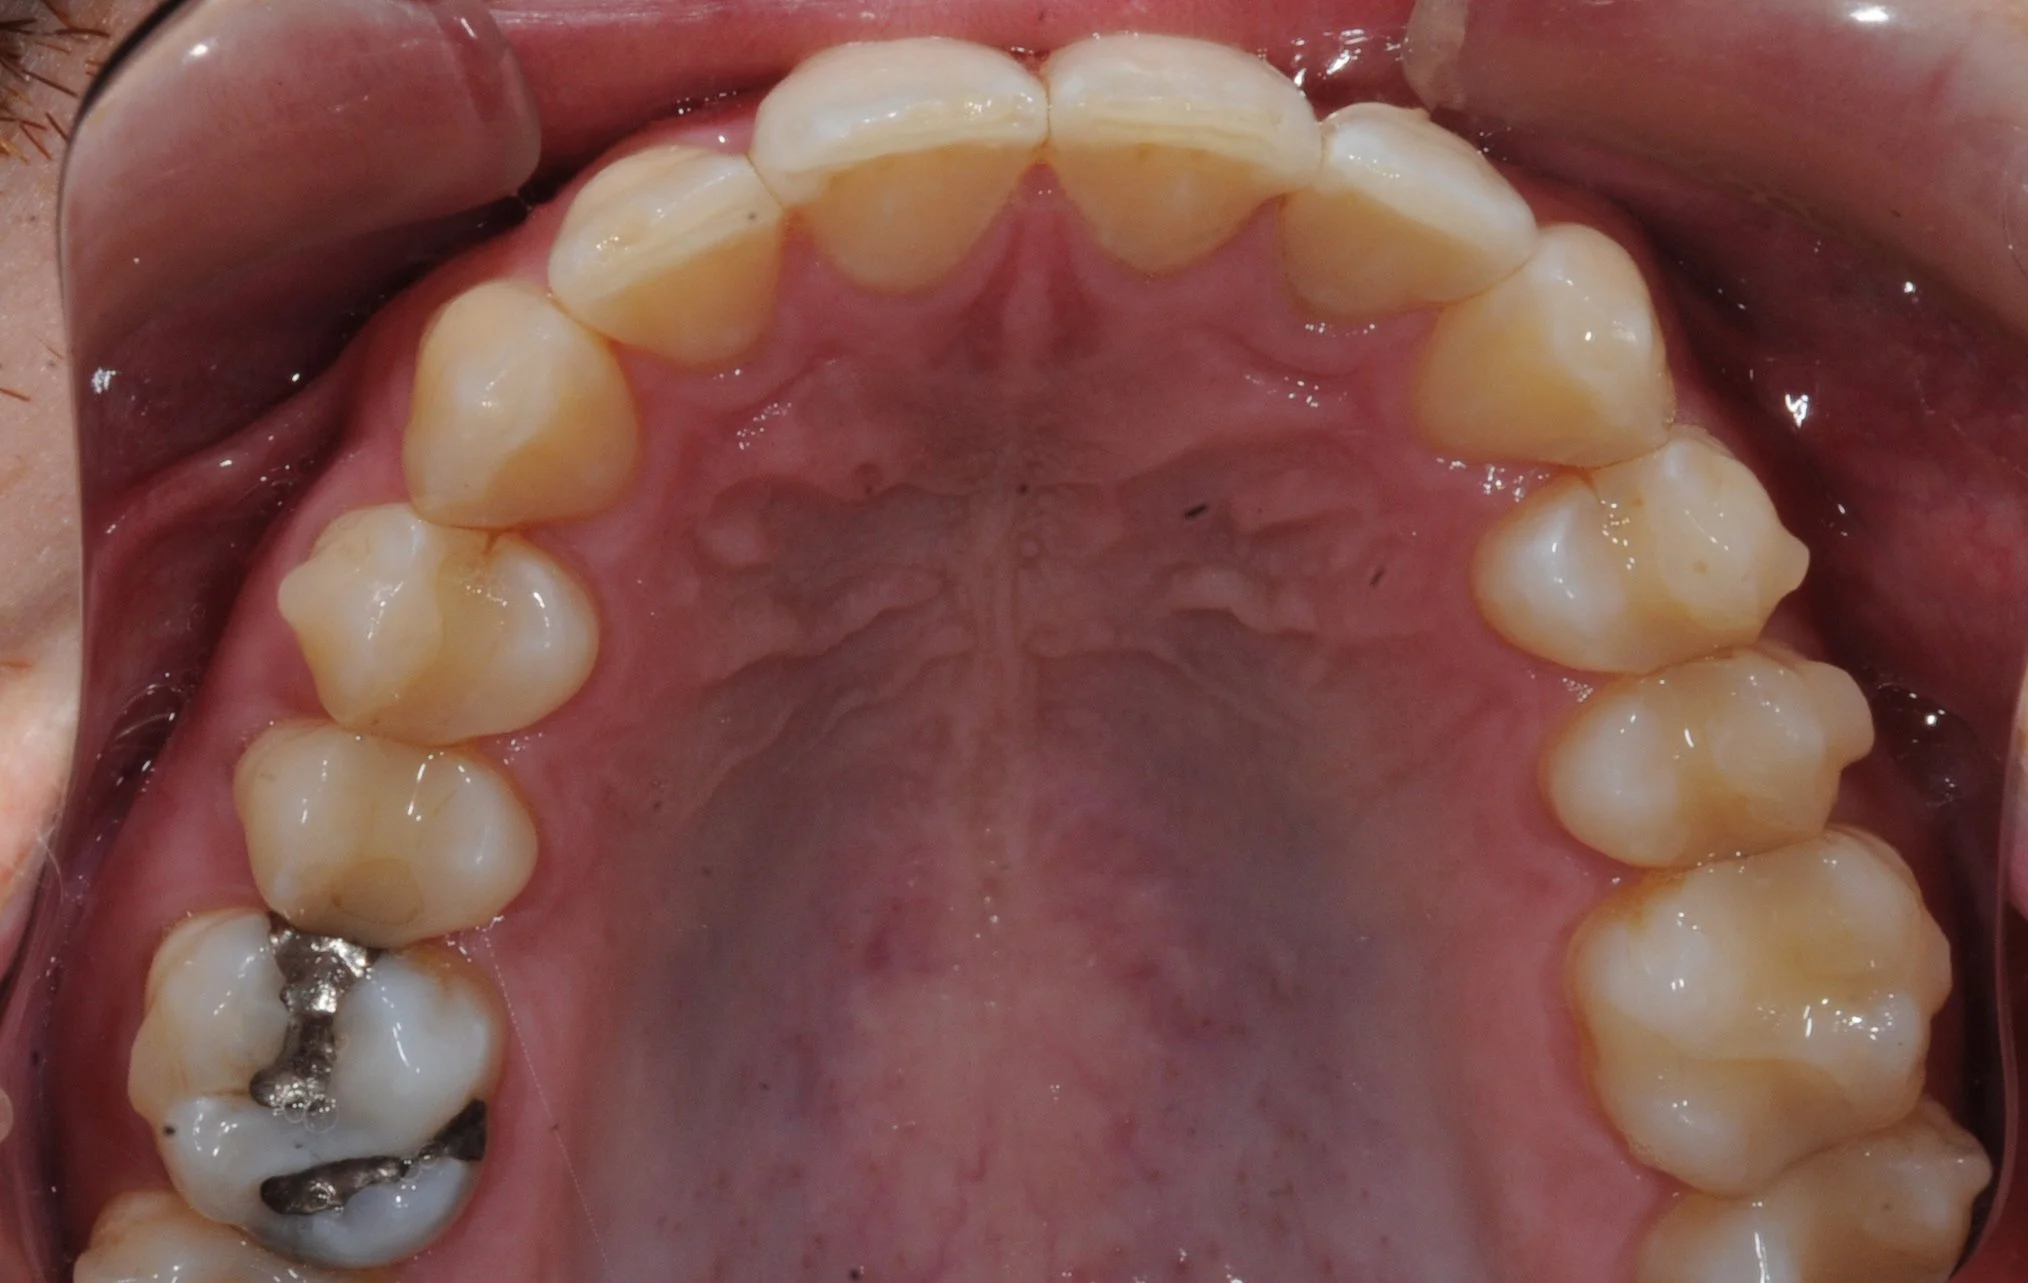

Walker’s Smile Transformation: Space Closed, Roots Aligned

The space created by the extraction has now fully closed, and the roots of his teeth have been aligned! Mission accomplished.

Closing the space while ensuring proper root positioning was a key step in achieving a stable and harmonious smile. With the roots now aligned, this patient’s teeth are not only esthetically pleasing but also positioned for long-term health and functionality.

Walker’s Smile Journey: A Stunning Finish in Just 1 Year!

These results are nothing short of amazing! Take a look at how well aligned his teeth are and how healthy the tissue on the bottom looks.

Here’s the big reveal: it took just 1 year to complete the treatment for his lower teeth with Inbrace! In fact, the Inbrace system finished aligning the lower arch faster than the upper aligners. A testament to the predictability of the Inbrace system.